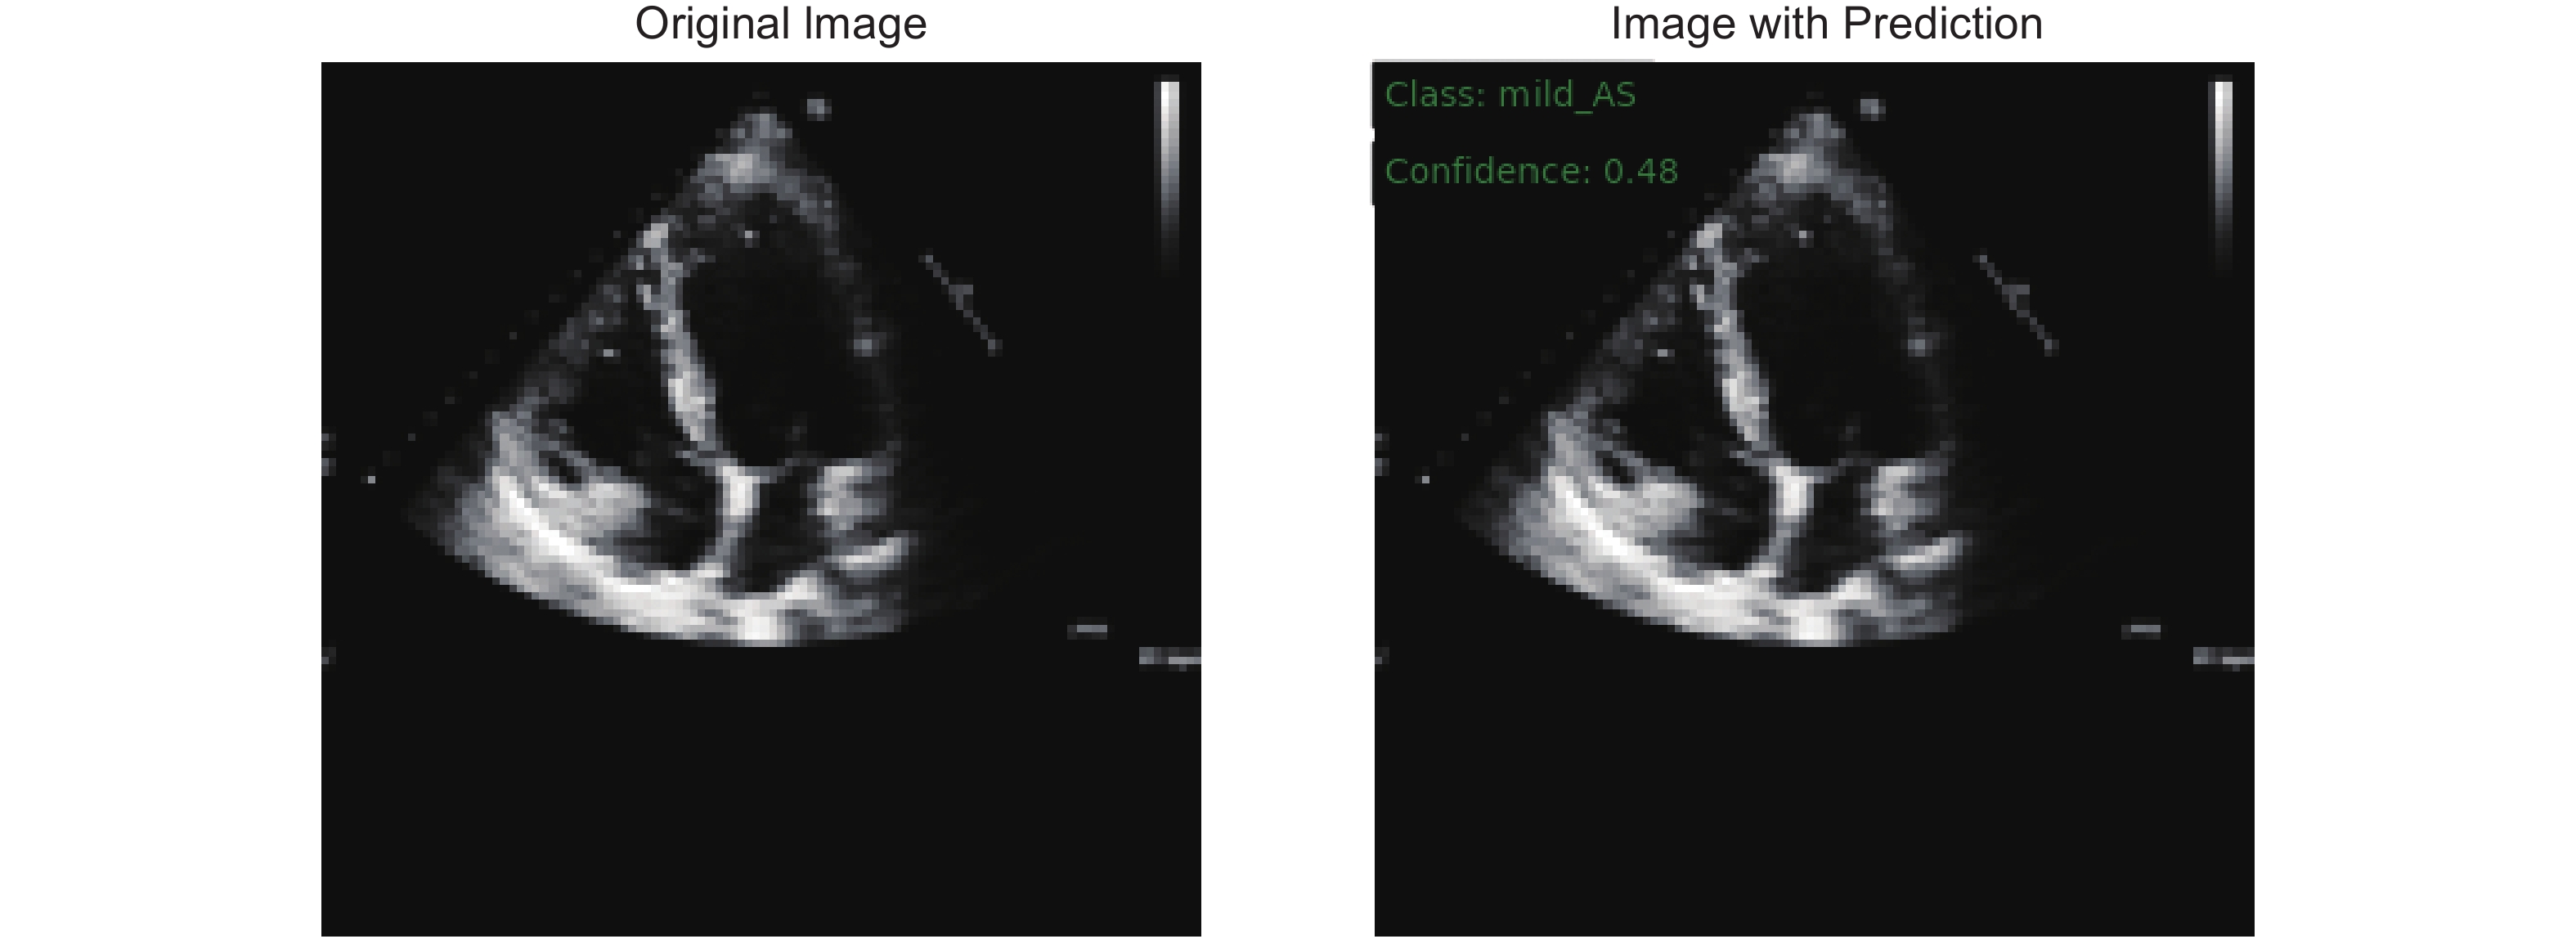

Holste G, Oikonomou EK, Mortazavi BJ, Coppi A, Faridi KF, Miller EJ, et al. Severe aortic stenosis detection by deep learning applied to echocardiography. Eur Heart J 2023; 44: 4592-4604.

Krishna H, Desai K, Slostad B, Bhayani S, Arnold JH, Ouwerkerk W, et al. Fully automated artificial intelligence assessment of aortic stenosis by echocardiography. J Am Soc Echocardiogr 2023; 36: 769-777.

Huang Z, Long G, Wessler BS, Hughes MC. Tmed 2: a dataset for semi-supervised classification of echocardiograms. In DataPerf: Benchmarking Data for Data-Centric AI Workshop 2022.

Huang Z, Long G, Wessler B, Hughes MC. A new semi-supervised learning benchmark for classifying view and diagnosing aortic stenosis from echocardiograms. Machine Learning for Healthcare Conference 2021; 149: 614-647.